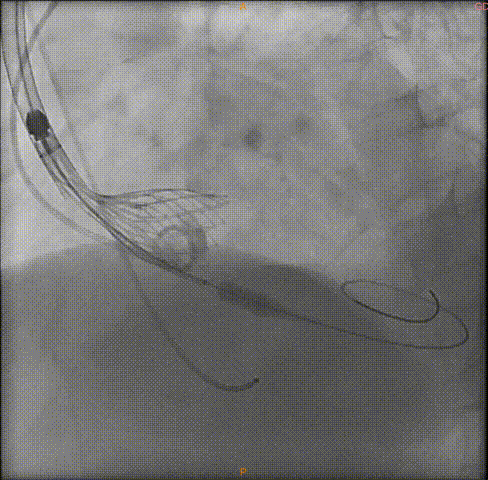

瓣膜释放

瓣膜完全释放前造影

完全释放中造影

释放后的造影

在多学科合作下,广州中医药大学第一附属医院心血管内科吴伟、李荣教授团队顺利完成全院首台高龄患者TAVR手术,经过3个小时的紧张有序操作,术中借助VitaFlow Liberty™瓣膜段柔顺性、可360度弯曲的功能顺利过弓,更是凭借心通医疗可回收系统自带内联鞘的功能,省去大鞘为血管入路差的患者带来更多选择,术后超声血管造影下肢入路无夹层且血管无破损,病人术后恢复良好,第三天即可下床活动。